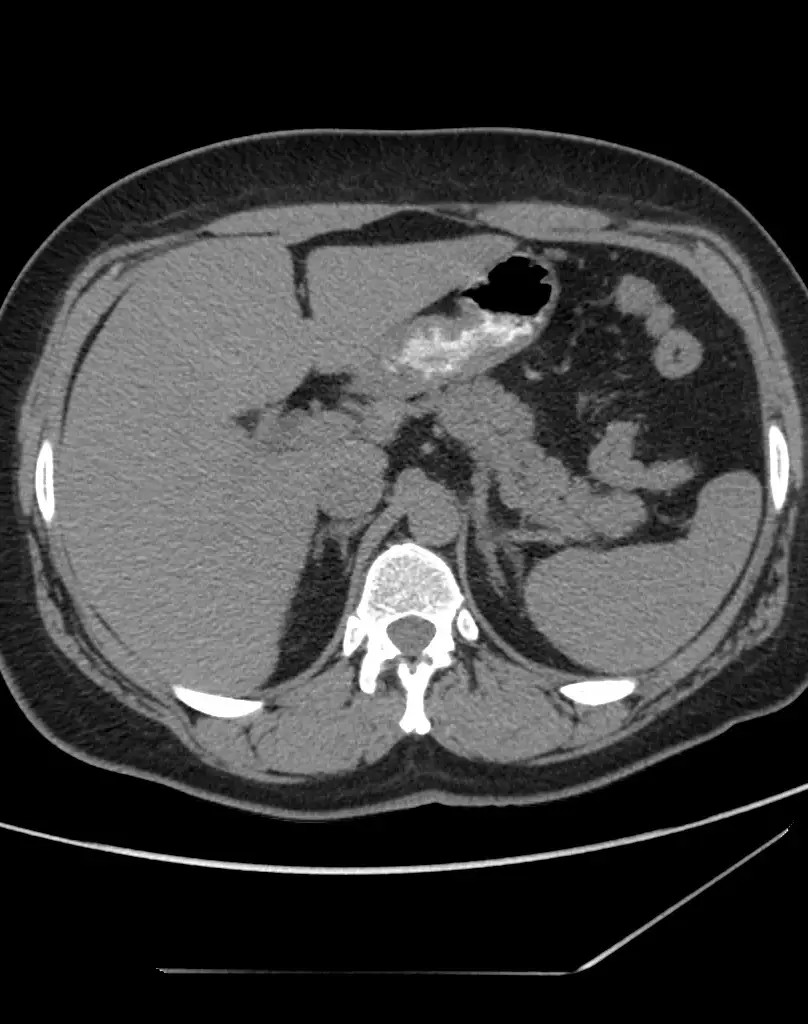

Исследование с контрастом - Примавист (ОБП, оценка печени)

Primovist (Примавист) — это специализированное контрастное вещество, предназначенное для исследования печени.

— При подозрении на опухоли, метастазы, гемангиомы, аденомы, кисты печени;

— Для оценки функции печени и характера новообразований;